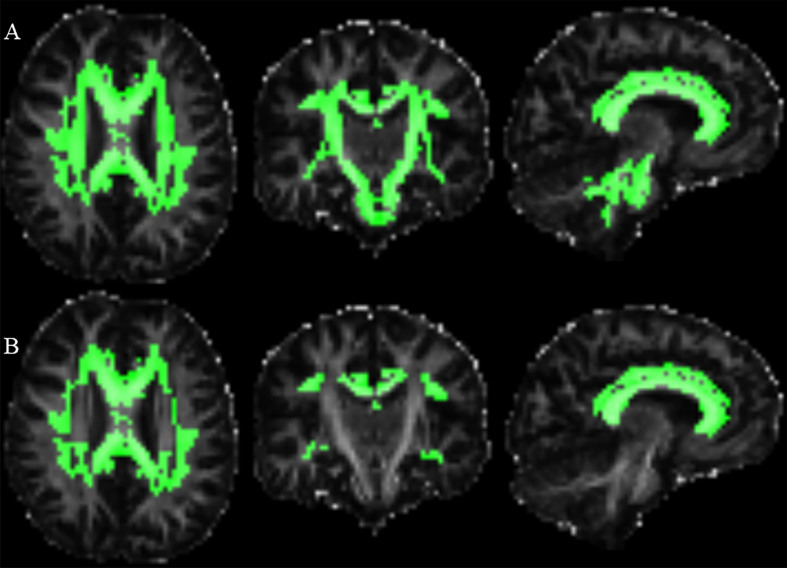

Results: Compared to controls, mHTT carriers exhibited WM changes in DKI and DTI. There were 22 more regions showing significant differences in HD detected by MK than FA. Only MK in five brain regions showed significantly difference between any two group, and negatively correlated with the disease burden (r = -0.80 to -0.71). ROC analysis revealed that MK was more sensitive and FA was more specific, while Youden index showed that the integration of FA and MK gave rise to higher authenticities, in distinguishing m& lCAP from controls (Youden Index = 0.786), and discerning different phase of HD (Youden Index = 0.804).

Conclusions: Microstructural changes in WM occur at early stage of HD and deteriorate over the disease progression. Integrating DKI and DTI would provide the best accuracies for differentiating early HD from control and identifying advanced HD.